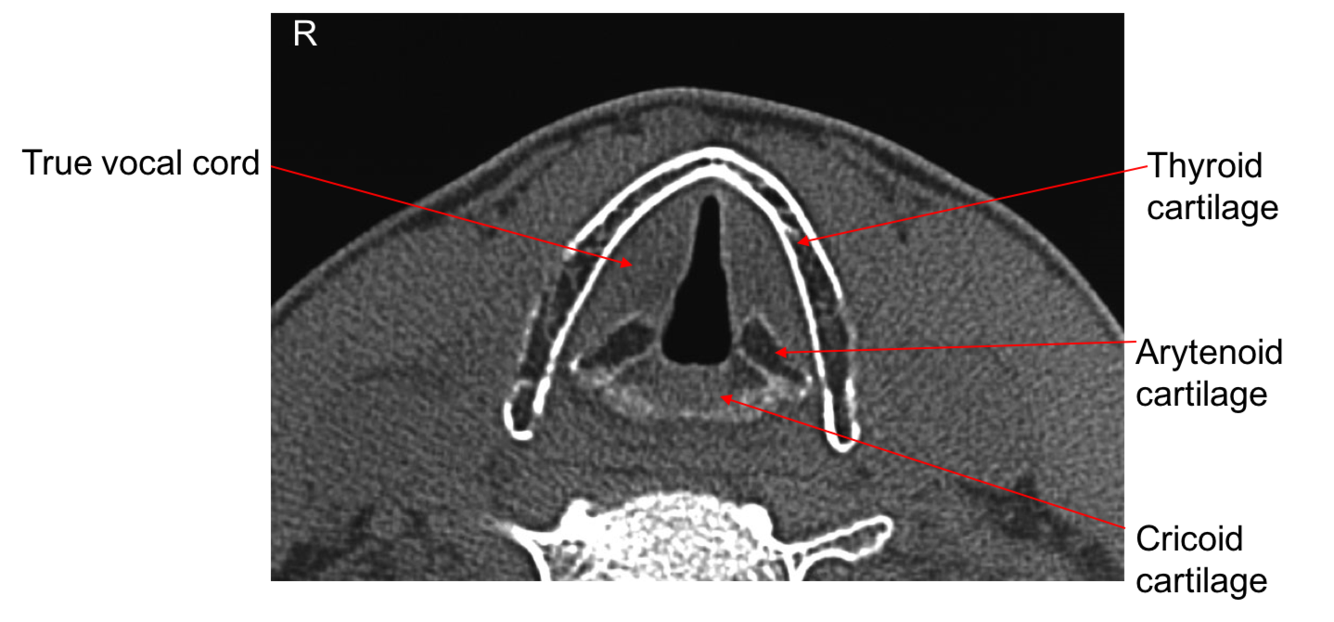

Label this superior view of the larynx

Label this image

Wall of larynx composed of nine pieces of cartilage held together by membranes & muscle fibres. Three of the pieces of cartilage are single (thyroid, epiglottis, cricoid) three are paired (arytenoid , cuneiform, corniculate)

Arytenoid most important as influence positions and tensions of vocal cords.